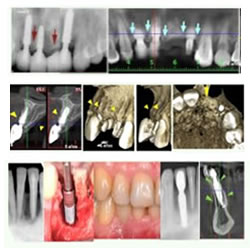

¿Cómo se colocan los implantes dentales?

Las restauraciones con los implantes dentales se llevan a cabo en dos fases. La primera fase consiste en la colocación quirúrgica del implante o los implantes en la mandíbula. Esto se lleva a cabo en el consultorio de su especialista implantológico. La colocación del implante es muy precisa, una vez en su sitio el tejido de la encía cubre el implante por un periodo curativo de tres a seis meses. Durante este tiempo el implante se une permanentemente al hueso.

Como los huesos de los maxilares tienen muy pocos nervios, el procedimiento de colocación causará solo una pequeña molestia y usted sanará pronto. Su dentista procurará que se sienta cómodo a través de todo el periodo de espera. Usted podrá usar su propia dentadura hasta que se complete el tratamiento.

La segunda fase consiste en la construcción del diente o dientes de remplazo (prótesis). Cuando el periodo de curación haya terminado, su dentista descubrirá la parte superior del implante dental usando un procedimiento rápido y sencillo. Entonces, usará el implante como la base sólida para restaurar sus dientes.

Su dentista recomendará el tipo de restauración que sea mejor para usted. Las opciones incluyen coronas para reemplazar un solo diente, puentes cuando faltan varios dientes y dentaduras fijas. Cada opción será evaluada cuidadosamente para su caso individual.